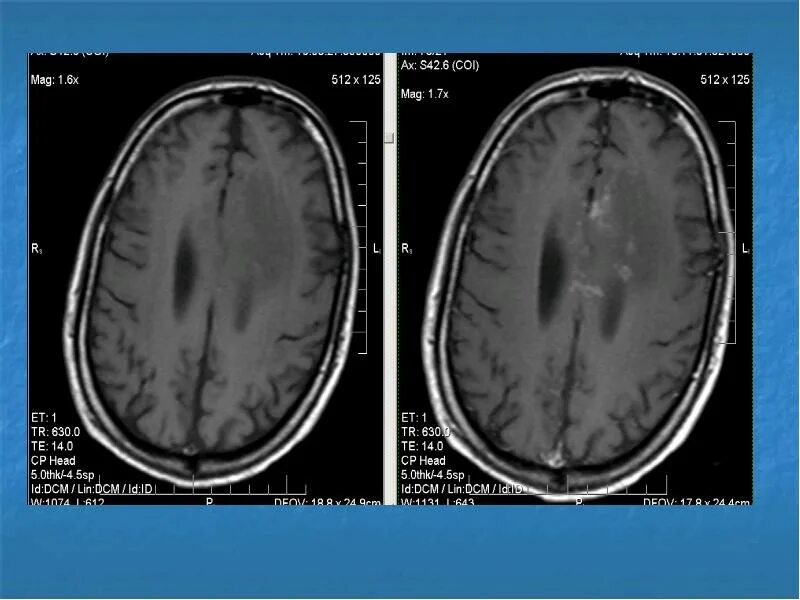

Очаговые и диффузные изменения вещества мозга